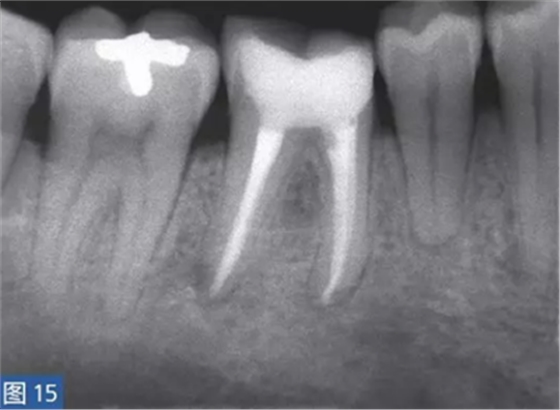

圖15:根管治療12 個(gè)月后的放射學(xué)檢查?;谂R床診斷,只有46 牙齒需要治療,因?yàn)樗歉獠∽兊闹饕±碓?